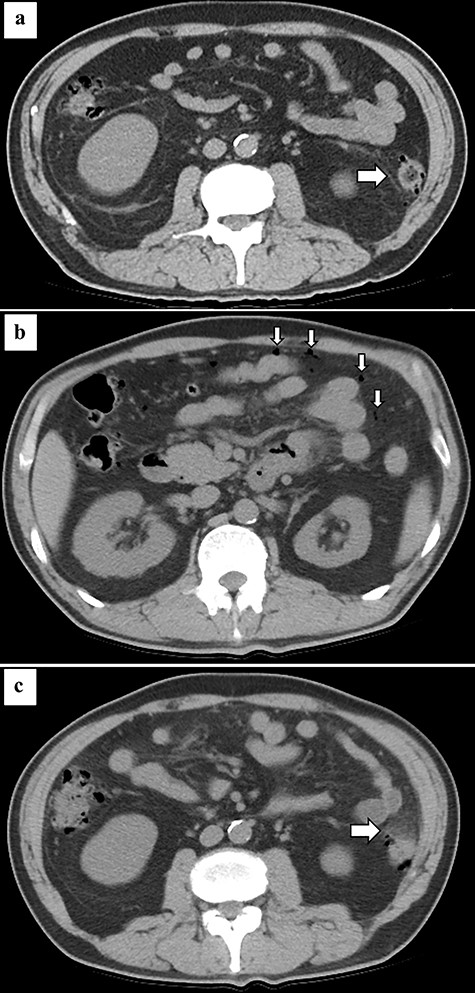

A 59-year-old man with a history of hypertension, type II diabetes mellitus, old myocardial infarction and chronic heart failure suffered from COVID-19 pneumonia 8 months prior to admission (Fig. 1). He required an artificial respirator on the ninth day of onset due to worsening of respiratory status. He underwent tracheotomy on the 19th day of onset. Two COVID-19 polymerase chain reaction (PCR) tests conducted on the 32nd day after the initial infection showed negative results. He was discharged on the 52nd day of onset. Six months after discharge, he presented with sudden abdominal pain and was admitted to our hospital. His vital signs were temperature, 35.1°C; heart rate, 74 beats per minute; blood pressure, 121/92 mmHg; and SpO2, 100% on room air. Physical examination showed board-like rigidity and rebound tenderness over the entire abdomen. Laboratory results showed significant increase in inflammatory response, with a white blood cell count of 18 000/μl. Computed tomography (CT) revealed ascites, free air in the abdominal cavity, multiple diverticula of the descending colon (Fig. 2b) and increased fat density surrounding the descending colon (Fig. 2c). We diagnosed the patient with colonic perforation and performed emergency surgery. Surgical findings revealed pinhole perforation in the descending colon (Fig. 3). As the perforation was small and there was no fragility of the surrounding colonic tissue, the perforation was sutured and closed. Then, the sutured site was covered with epiploicea appendices. A drain was placed in the left paracolic gutter after abdominal cleaning. The abdominal wall was closed without a diverting stoma. The patient was wheezing on the first postoperative day, and he required oxygenation when SpO2 dropped to 70% on room air. His COVID-19 PCR test was negative. The cardiothoracic ratio, which was 40% preoperatively, increased to 50%. He was diagnosed with exacerbation of chronic heart failure and was treated with diuretics, and his symptoms improved. He passed without any complications, and he was discharged from the hospital 13 days after the operation.

Abdominal CT at the onset of COVID-19 showing diverticulum of the descending colon (arrow) (a). Abdominal CT at the onset of pan-peritonitis showing free air in the abdominal cavity (arrow) (b) and increased fat density surrounding the descending colon (arrow) (c).